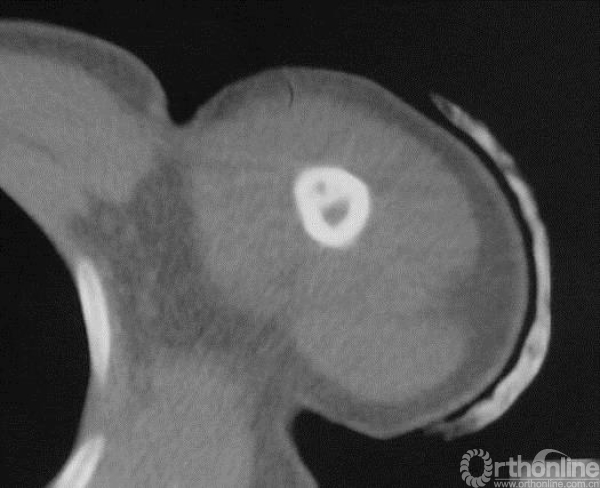

图13-2 病例一伤后CT轴位骨窗

病例一:X线平片见病变内基质不均匀呈虫噬样破坏,边界不清楚,皮质骨受侵破坏。提示疾病具有一定的侵袭性表现。